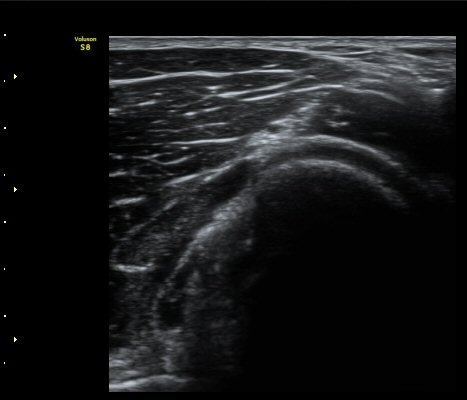

ŽÃËÀÚ¸¦ Á» ´õ ¸»´ÜÀ¸·Î À̵¿ÇÏ´Ï ³¶Á¾Àº ´õ Å©°Ô °üÂûµÈ´Ù(±×¸² 3, 4).

¿ä°ñÀ» Á¾´Ü¸éÀ¸·Î °üÂûÇÏ´Ï ¿ä°ñ ±ÙÀ§ºÎ Ç¥Ãþ¿¡ ³¶Á¾ÀÌ È®Àεǰí(±×¸² 5) ŽÃËÀÚ¸¦

Á¶ÀýÇÏ´Ï Èİñ°ß½Å°æÀÇ Á¾´Ü¸é À̹ÌÁö°¡ °üÂûµÇ´Âµ¥ ³¶Á¾¿¡ ÀÇÇØ Ç¥ÃþÀ¸·Î ÀüÀ§µÇ¾î

ÀÖ´Ù(±×¸² 6,7). ±×¸² 8. ³¶Á¾°ú Èİñ°£½Å°æ ÁÖÀ§¾Ö¼­ °üÂûµÇ´Â µ¿¸Æ.